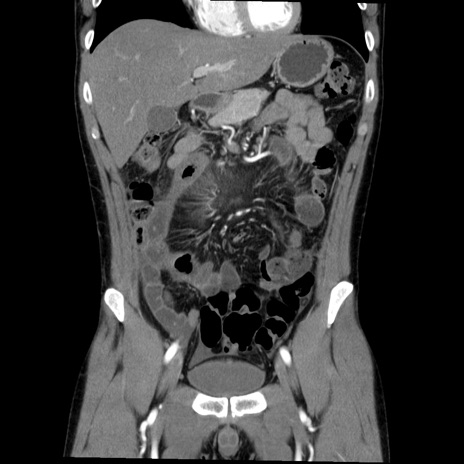

症例36(冠状断像)

【症例】20歳代 男性

【主訴】心窩部痛

【現病歴】今朝より上腹部痛あり。一旦軽快していたが再度出現したため救急要請。昨日夕に白身の魚を含む刺身を食べた。

【身体所見】BP 136/89mmHg、HR 74/min、BT 37.0℃、腹部:膨満、軟、心窩部に圧痛あり。反跳痛なし、筋性防御なし、腸雑音やや亢進あり。

【データ】WBC 17700、CRP 0.48